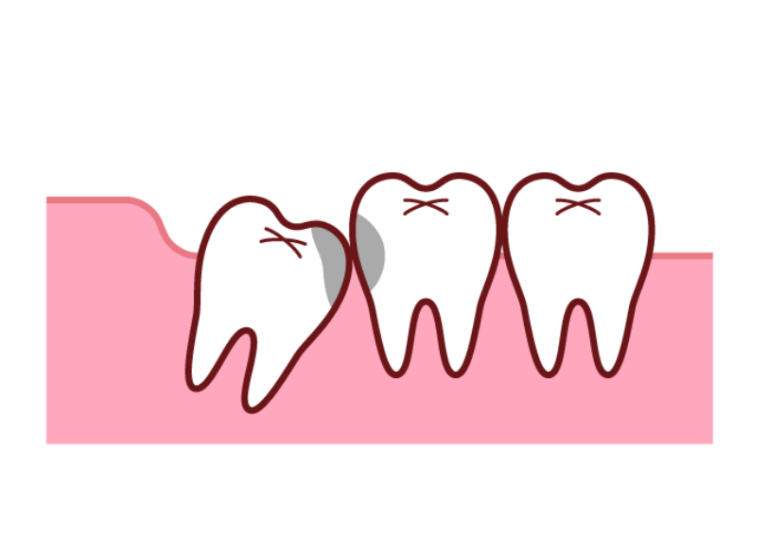

横や斜めに生えてくる

スペース不足のためまっすぐ上に出てくることができず、横向きや斜めに傾いて生えてきてしまうケースです。

隣にある大切な奥歯(第二大臼歯)をぐいぐいと押し続け、歯並び全体を乱してしまったり強い痛みの原因となったりします。

歯茎に埋まったまま(埋伏歯)

骨の中に完全に埋まったままだったり、頭の一部だけが歯茎から顔を出していたりするケースです。

中途半端に顔を出していると歯と歯茎の間に深い溝ができ、そこに汚れが溜まって歯茎がひどく腫れ上がる「智歯周囲炎」という炎症を繰り返し引き起こすことがあります。

また骨の中に埋まったままでも隣の歯の根を溶かしてしまったり、大きな袋(嚢胞)を作ってしまったりする原因となることもあります。